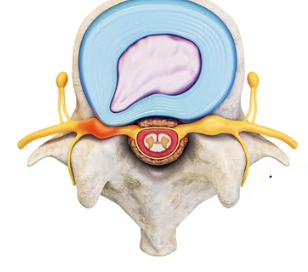

허리디스크는 많은 현대인들이 겪고 있는 흔한 질환 중 하나입니다. 이는 척추 뼈 사이에 위치한 디스크가 손상되어 신경을 압박하게 되면서 발생하는 통증과 다양한 증상을 유발합니다. 전조증상으로는 허리의 불편함과 통증이 점차적으로 시작되며, 이는 다리까지 방사되는 경우도 있습니다. 조기 발견과 적절한 치료가 중요한데, 이는 증상의 악화를 막고, 더 나은 삶의 질을 유지할 수 있게 도와줍니다. 비수술적 치료방법부터 수술적 치료까지 다양한 옵션이 있으며, 환자의 상태와 증상에 따라 최적의 치료 계획을 세울 수 있습니다. 이 글에서는 허리디스크의 전조증상을 인지하는 방법과, 효과적인 치료 방안에 대해 자세히 알아보겠습니다. 오늘은 허리 디스크 전조증상 및 치료방법에 대해 알아보겠습니다.

허리디스크는 많은 현대인들이 겪고 있는 질환 중 하나로, 척추의 디스크가 탈출하거나 손상되어 신경을 압박함으로써 발생하는 통증 및 기타 증상을 일으키는 상태를 말합니다. 이 질환은 잘못된 자세, 과도한 체중, 또는 반복적인 스트레스 등 다양한 원인에 의해 발생할 수 있으며, 특히 장시간 앉아 있는 생활습관이 있는 사람들에게서 자주 발견됩니다. 전조증상으로는 허리 통증, 다리 저림, 감각 이상 등이 있으며, 이러한 증상들은 일상생활에 큰 불편을 초래할 수 있습니다. 치료 방법은 증상의 정도와 개인의 상태에 따라 다르지만, 일반적으로는 물리치료, 약물치료, 그리고 필요한 경우 수술적 치료가 고려될 수 있습니다. 조기 진단과 적절한 치료 계획을 통해 허리디스크로 인한 통증과 불편을 줄이고, 건강한 척추 상태를 유지할 수 있습니다.